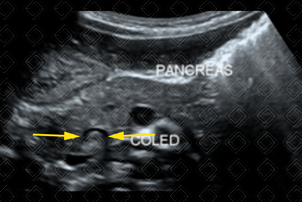

Texto alternativo para a imagem Figura 2. Créditos: Dra. Elazir Mota - Rio de Janeiro/RJ

Descrição das figuras 1 e 2 : Ultrassonografia de abdome. Imagem ecogênica no colédoco distal (setas amarelas).

• Ultrassonografia de abdome: Bom exame para avaliação inicial das vias biliares intra e extra-hepáticas. No entanto, deve ser realizado por radiologista experiente. Na imagem, o cálculo caracteriza-se por imagem ecogênica, podendo haver ou não sombra acústica posterior (figuras 1 e 2);